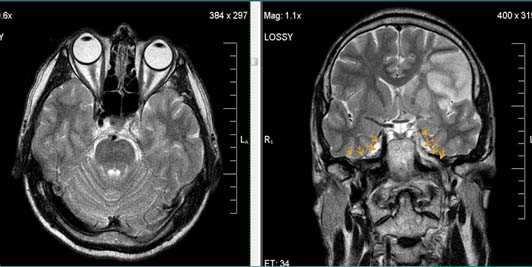

Внутримозговая гематома (граница острой и ранней подострой стадий - 3 суток), осложнившаяся внутрижелудочковым кровоизлиянием.

Внутримозговая гематома, поздний подострый период (14-21 день) с перифокальным отеком вокруг гематомы.

Внутримозговая гематома правой теменной доли. Граница поздней подострой и ранней хронической стадии. В Т2-ВИ виден ободок гемосидерина (стрелка).

Хочется подчеркнуть возможность МРТ в выявлении последствий геморрагического поражения - остается хорошо дифференцируемый по Т2 ободок гемосидерина, недоступный для визуализации при других методах нейровизуализации.

Стрелками показан ободок гемосидерина по периферии постишемической кисты.